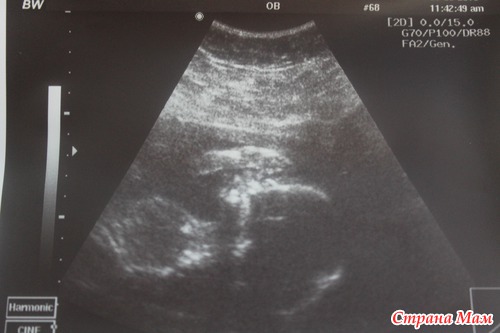

... До первого УЗИ, подарившего нам столько эмоций

где мы с трепетом разглядывали крохотные ручки и ножки, до первых пиночков и шевелюшек...